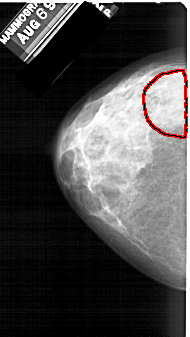

FILE: A_1391_1.LEFT_MLO.OVERLAY

TOTAL_ABNORMALITIES 1

ABNORMALITY 1

LESION_TYPE CALCIFICATION TYPE PLEOMORPHIC DISTRIBUTION SEGMENTAL

ASSESSMENT 4

SUBTLETY 4

PATHOLOGY BENIGN

TOTAL_OUTLINES 1

BOUNDARY